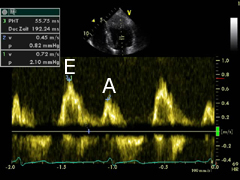

E/A Ratio

- Measure of diastolic dysfunction

- PW doppler across MV in apical view

- Rule 1: Normal diastolic function if echo normal, age<45 yrs, E>A

- Rule 2: Impaired relaxation if A>E, with E/A<1

- Rule 3: Pseudonormal if echo abnormal (LVH), age>65, E>A, E/A>1

- Rule 4: Restrictive filling if E/A>2